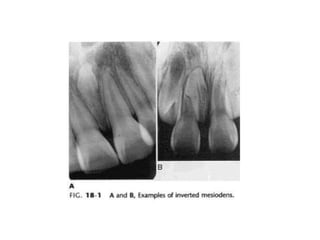

1. Supernumerary Teeth

Merupakan gigi yang jumlahnya melebihi

jumlah normal.

• Mesiodens